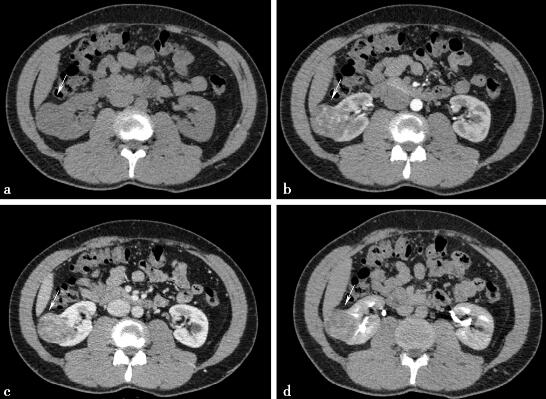

病例4-2-1:CT平扫和增强。

图1a,轴位平扫。图1b~d,动态增强,右肾中极可见一软组织异常密度影,平扫呈等低密度,增强后动脉期可见不均匀性强化,排泄期为低密度